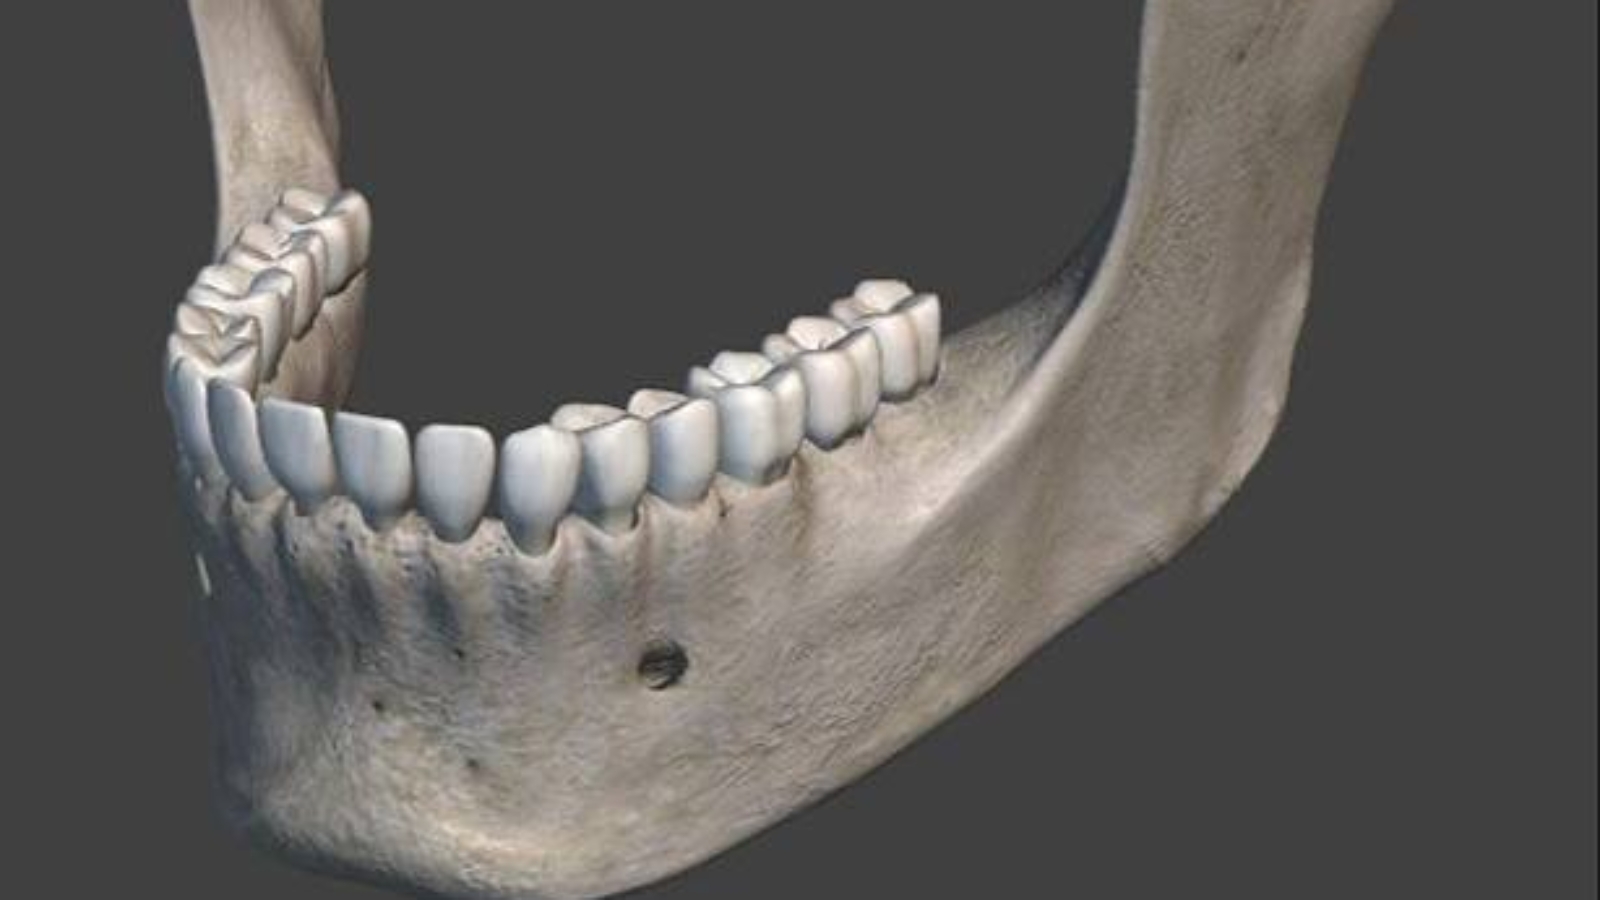

The lower jaw is a key element of the dentofacial system, determining not only masticatory function but also the stability of occlusion, the performance of the temporomandibular joints, and the overall balance of facial anatomy. In the clinical practice of Professor Alexander von Breuer, particular attention is given to the relationship between mandibular position and the functional condition of the entire system, as this structure defines load distribution and movement dynamics. At DentalClinic24, the lower jaw is not considered an isolated anatomical unit, but a central coordinating structure that directly influences diagnostic accuracy and treatment effectiveness.

The anatomical role of the lower jaw extends beyond mechanical function, as it contributes to facial profile formation, supports soft tissues, and influences overall facial aesthetics. Changes in its position may affect chin alignment, facial symmetry, and the visual perception of the lower third of the face. At DentalClinic24, aesthetic considerations are always evaluated in conjunction with functional parameters, as visible changes are understood as the result of underlying structural processes rather than isolated concerns.

Precise diagnostics play a defining role in evaluating mandibular condition, as the clinical picture is shaped by multiple interconnected factors. Assessment includes analysis of jaw position at rest and during movement, joint condition, occlusal relationships, and muscular interaction. At DentalClinic24, the diagnostic process is designed to identify not only obvious disturbances but also subtle functional imbalances that may influence treatment outcomes.